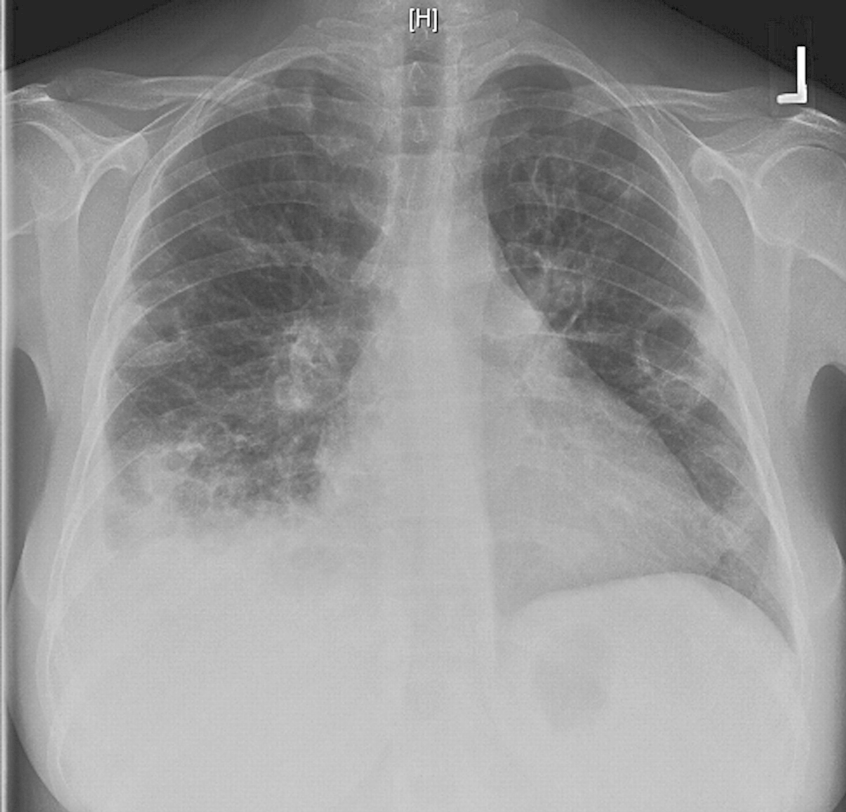

CLINICAL HISTORY:

35yo Male

Chest pain and Dyspnoea

Active IVDU

FINDINGS:

Lungs are slightly underinflated.

Multiple cavitating lesions of varying size distributed throughout both lungs with no apparent zonal predominance.

Small/moderate right sided pleural effusion.

The heart appears borderline enlarged but there is no evidence of heart failure. Both hilar contours appear abnormal but this may be due to superimposed lesions. Mediastinal contours are otherwise normal.

Skeletal review is unremarkable.

IMPRESSION:

Given the clinical context appearances are in keeping with multiple septic pulmonary emboli.

BACKGROUND INFORMATION:

DIFFERENTIAL DIAGNOSIS:

FOLLOW-UP: